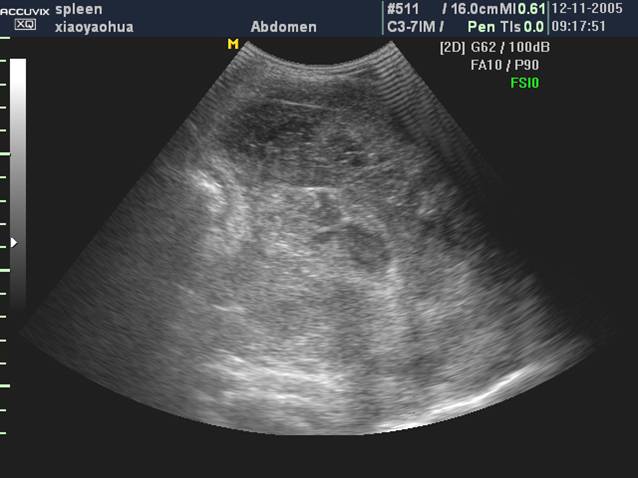

声像表现

1、弥漫性脾肿大

脾脏增大,实质为均匀性中等回声或低回声

2、局限性病变

小结节型<1cm,大结节型1~3cm,大块型> 3cm

结节一般圆形或椭圆形,境界清晰

低回声,类囊肿回声